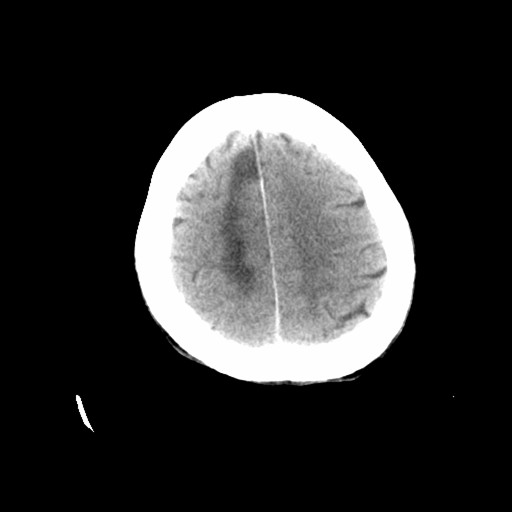

标题: CT19998:男,68岁,突然偏瘫一天 [打印本页]

标题: CT19998:男,68岁,突然偏瘫一天

考虑右侧额顶叶脑梗塞。